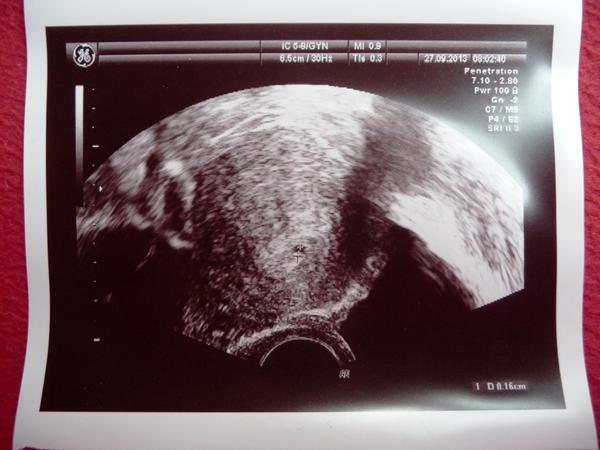

@viaven no vkladali mi 2 blastocysty, jedna uz vyliezajuca, pripravena na zahryznutie 😝 a pregnyl mi pichali uz 2 dni pred punkciou, cize dnes je to uz 9.den teoreticky. a mala som ET + 2 embryjka sme zamrazili